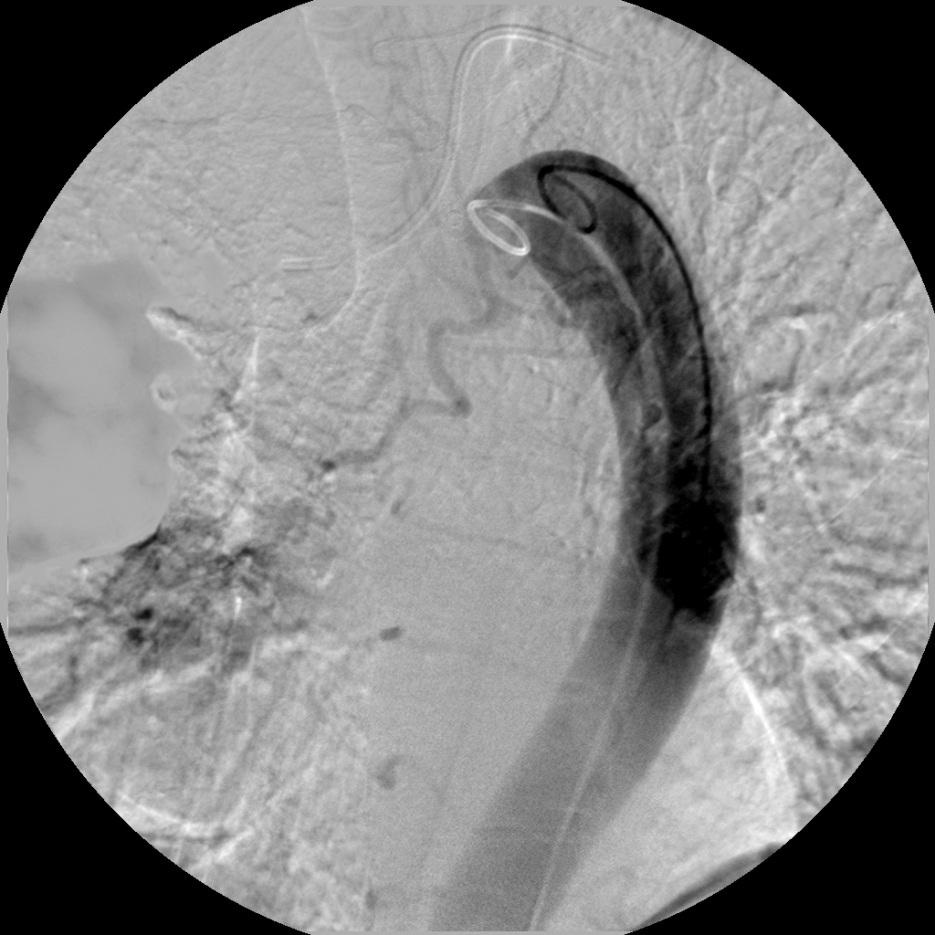

降主动脉造影,左前斜位(猪尾巴导管)证实支气管动脉开口位于主动脉弓下缘

造影剂总量30ml,15ml/秒注射 |